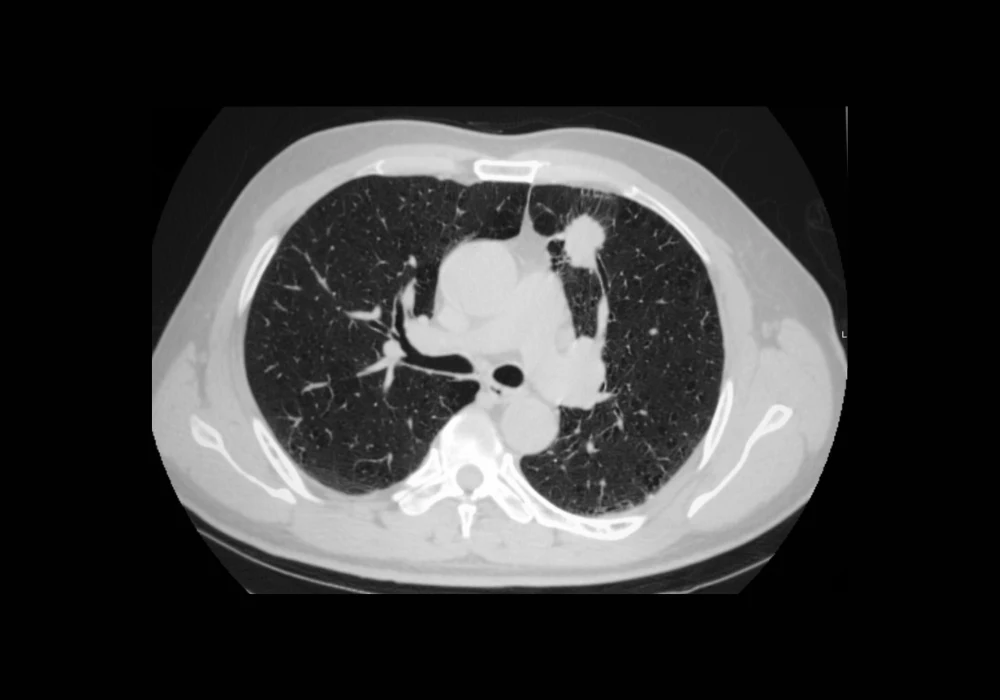

Accurate identification and quantification of lung cancer lesions is critical for diagnosis, staging, treatment planning and disease monitoring. While primary tumours receive most attention in radiological evaluations, patients often present with multiple lesions that must also be assessed for a complete picture of disease burden. Traditional manual segmentation remains laborious and subject to variability, making it less suitable for large-scale or real-world clinical use. A new automated pipeline now offers promising results for segmenting multiple lesions in computed tomography (CT) scans across diverse clinical settings, potentially improving consistency, sensitivity and efficiency in lung cancer management.

On the internal test dataset, the pipeline achieved a lesion-level Dice similarity coefficient (DSC) of 81%, an image-level DSC of 76% and a lesion detection sensitivity of 85%. These results outperformed conventional architectures such as Swin-UNet, U-Net++ and UResNet when trained on the same data. Even with larger lesions, which are typically more clinically significant, the segmentation remained accurate, and volume measurements showed high agreement with manual annotations.

External validation on the ChAImeleon dataset confirmed the pipeline’s generalisability, with a lesion-level DSC of 78% and an image-level DSC of 73%. Lesion detection sensitivity remained high at 85%, although precision was slightly lower due to more variable imaging conditions. Despite this, the correlation between predicted and manual volume measurements remained strong, with minimal bias and narrow agreement limits.